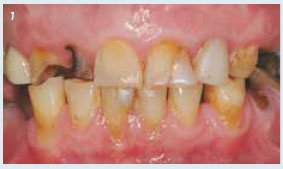

Afb. 3

Na verwijderen van de wattenrollen kunnen de cuspidaten worden opgebouwd en is mandibulaire stabiliteit verkregen.